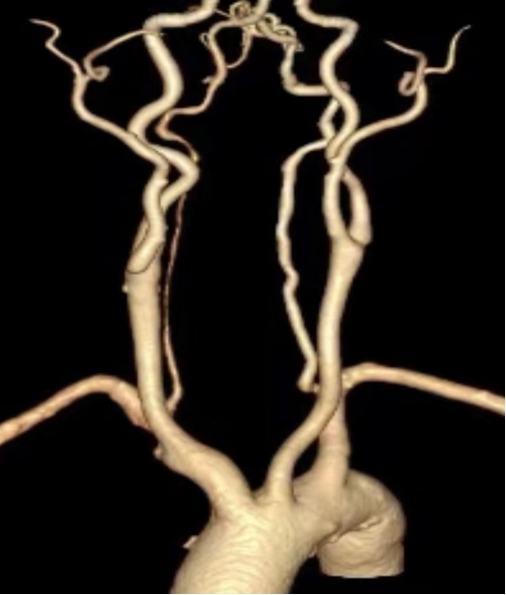

图:锁骨下动脉解剖结构

图:锁骨下动脉CT

术前评估的关键:CTA成像

CTA是评估主动脉弓上病变的常规且重要的术前检查方法。通过CTA,我们需要重点评估以下信息:

• 主动脉弓的形态:I型、II型或III型主动脉弓,直接影响导管操作的难度。

• 病变的具体情况:包括病变位置(是否累及开口)、性质(狭窄或闭塞)、长度。

• 与邻近血管的关系:特别是椎动脉开口距离病变的距离。

• 入路的选择:根据病变和主动脉弓形态,规划股动脉、桡动脉或肱动脉入路,甚至双入路方案。